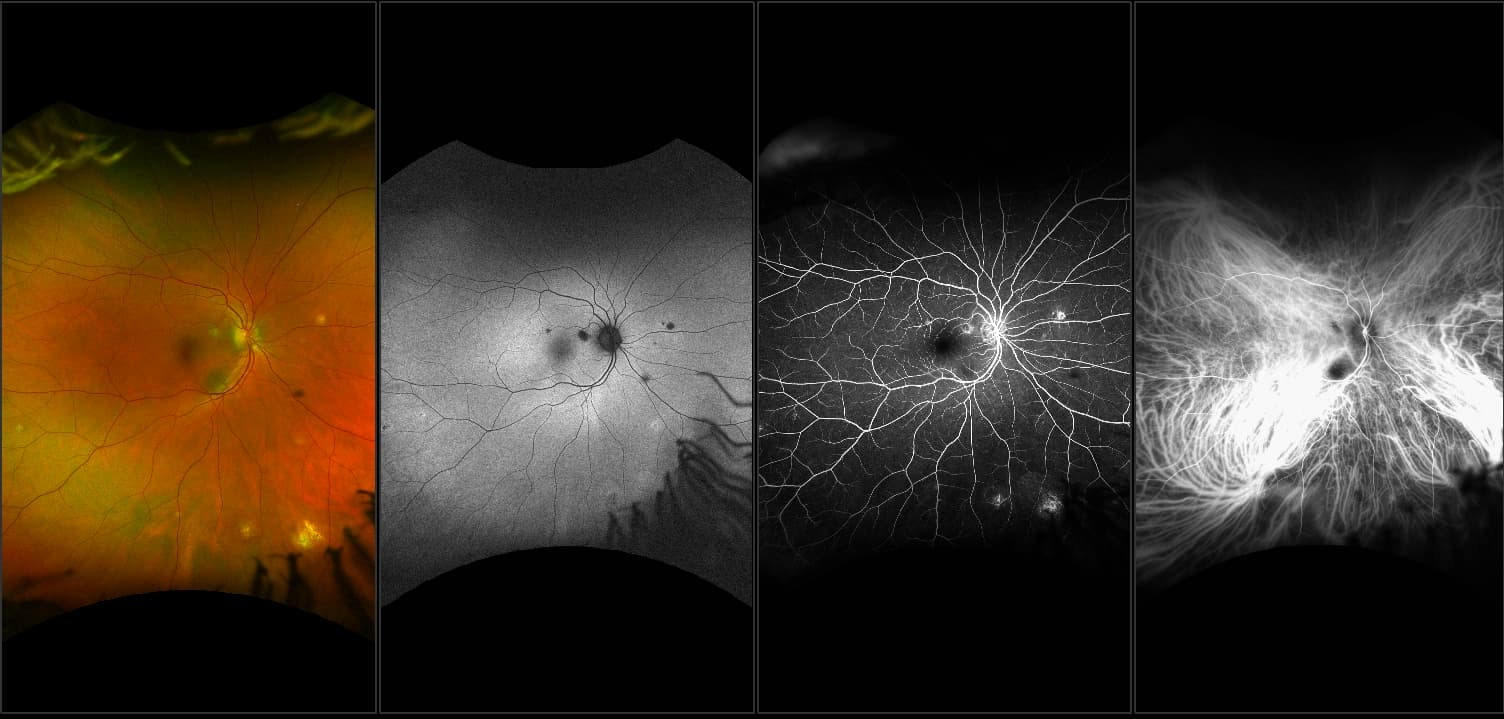

California - Uveitis, RG, AF, FA, ICG

What: Uveitis is an inflammation of any of the structures of the uvea: iris, ciliary body, or choroid. Uveitis is often captured using multimodal imaging. This case demonstrates how those imaging modes work together to help confirm a patient’s disease.

Why: A patient with uveitis was captured using optomap multimodal imaging. Images show inflammatory foci typical of uveitis in the mid to far periphery. These lesions correspond to each other on multimodal imaging. Interweave FA/ICG is often used when capturing uveitis. FA imaging may show pinpoint lesions and the ICG may help to confirm disease if lesions are seen in the ICG images.

In the picture: One study found that 59% of uveitis cases had peripheral findings on optomap icg.  Another study found that adding UWF imaging changed treatment in uveitis patients up to 48% of the time.